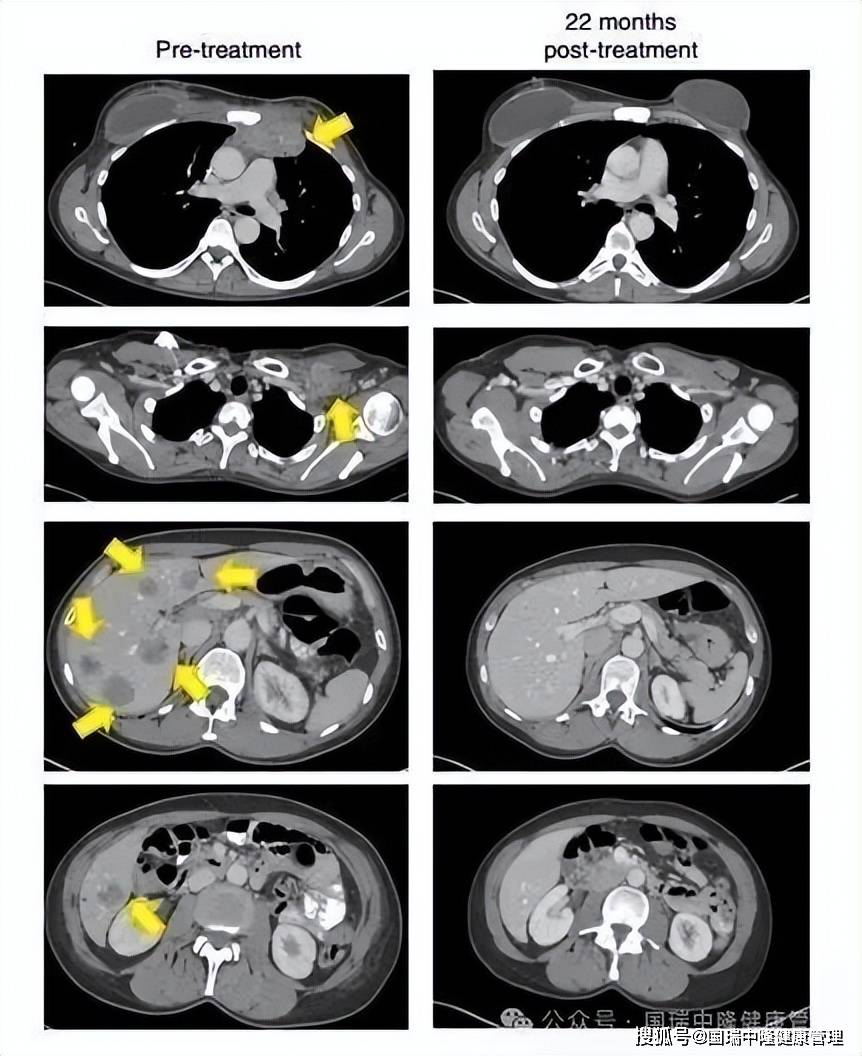

个案研究显示,晚期转移性乳腺癌患者经免疫细胞治疗后可实现肿瘤完全消退。国内团队也报道了DC-NKT/CTL方案帮助乳腺癌术后患者平稳度过5年复发高危期、实现临床痊愈的案例。

▲22个月后,这名患者的肿瘤(黄色箭头)消失得无影无踪